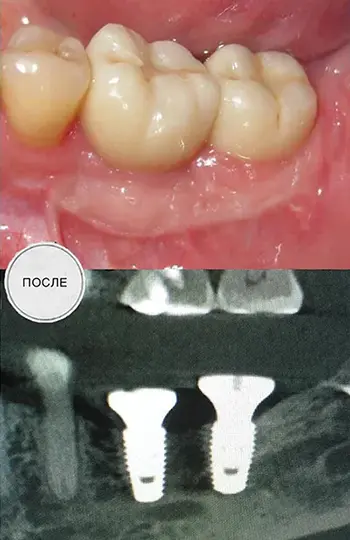

Імплантація

Збільшення обсягу кістки.

Після видалення кісти (не в нашій клініці) відсутні жувальні зуби, наскрізний дефект щелепи, в цій зоні нижньощелепний нерв проходить поза кістковими структурами. Пластика кістки та м’яких тканин, імплантація.

Хірург Святослав Вантурінов.

Цільноцирконієві коронки на гвинтовій фіксації.